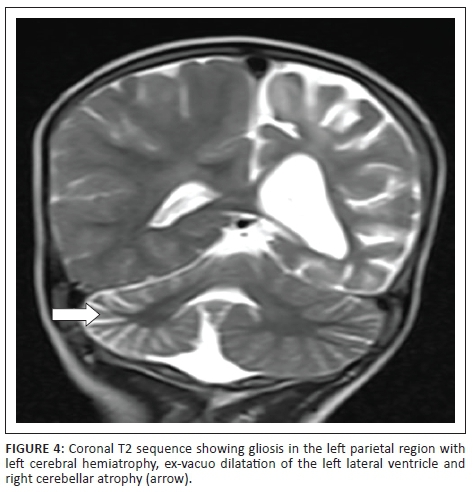

Magnetic resonance imaging (MRI) of the brain showed atrophy of the right cerebellar hemisphere with prominence of the cerebellar folia (Figure 1). Left cerebral peduncle was small in size suggestive of Wallerian degeneration (Figure 2). Left cerebral hemisphere was atrophic as evident from the prominence of sulcal spaces, sylvian fissure and ex-vacuo dilatation of the left lateral ventricle with the shift of midline structures towards left. An old infarct with gliosis was noted in left fronto-temporo-parietal region appearing hypointense on T1WI and hyperintense on T2WI and fluid attenuation inversion recovery with no restriction on diffusion weighted imaging. Associated uniform thickening of the calvarium was noted on the left side (Figures 3 and 4). Magnetic resonance angiography showed attenuation and reduced signal intensity of the M2 and M3 segments of the left middle cerebral artery (MCA) (Figure 5). A diagnosis of Davidoff-Dyke-Masson syndrome type III was made.